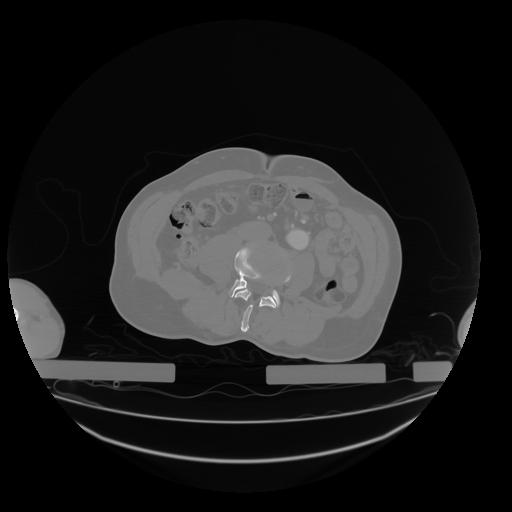

28 CUERPO,CE,Vol,2.0,CUERPO,,